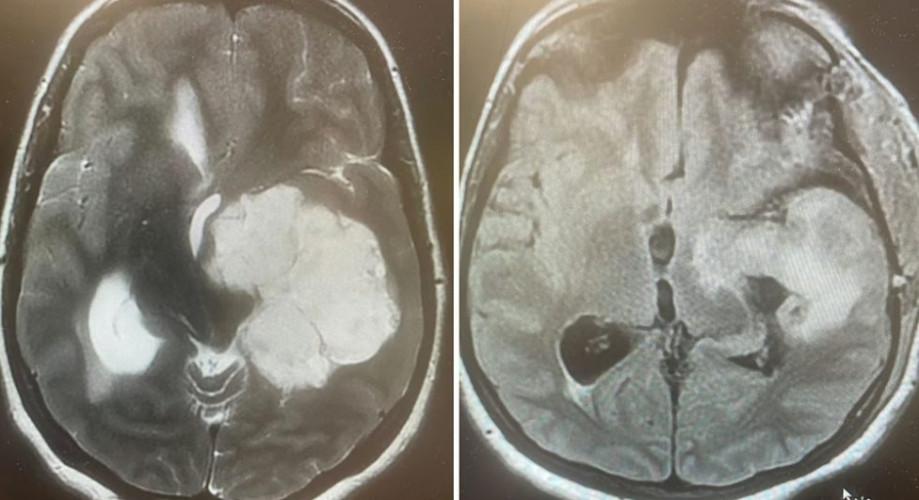

أعلن الفريق الطبي المتخصص في جراحة المخ والأعصاب بمستشفى الملك عبدالعزيز التخصصي، التابع لتجمُّع الطائف الصحي، نجاح عملية جراحية دقيقة ونادرة، أُجريت لشابة تبلغ من العمر 29 عامًا، تمثلت في استئصال ورم دماغي كبير ومستقر في الفص الصدغي الأيسر، ممتدًّا إلى قاعدة الجمجمة وجذع الدماغ.

وتسبب هذا الورم للمريضة في ضعف حركي تشنجي في الجهة اليمنى من الجسم، إلى جانب اضطراب في التوازن، واختلال في النطق والذاكرة.

وجرى تنفيذ العملية بتقنية مجهرية عالية الدقة عبر تداخُل جناحي صدغي موسع؛ ما أتاح للفريق الطبي استكشاف الشرايين الدماغية والأعصاب القحفية المهمة للحياة، وفصلها بعناية عن كتلة الورم؛ بهدف الحفاظ على سلامتها.

واستمرت الجراحة عشر ساعات متواصلة، نجح خلالها الفريق في إزالة الورم بالكامل دون المساس بالمراكز الحيوية والوظائف الأساسية.